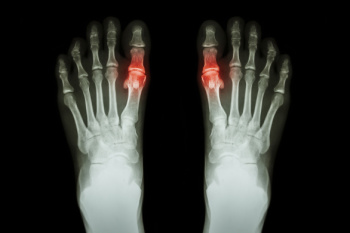

Stress fractures in the feet are small cracks in the bone that develop from repeated strain. They often occur when activity increases quickly or when the foot absorbs repeated impact, such as running or jumping. Pain usually begins gradually and worsens with movement, especially in weight-bearing bones like the long bones of the feet. Stress fractures can be difficult to detect early because swelling and bruising may be mild. A podiatrist can examine the foot, check for tender areas, and order imaging tests such as MRI scans to confirm the diagnosis. Treatment includes reducing stress on the bone and using supportive devices like walking boots, braces, or custom inserts. These help to limit movement and reduce pressure on the injured area as healing continues. Care also includes a guided return to activity to prevent long-term problems. If you have symptoms of a stress fracture after vigorous activity, it is suggested that you make an appointment with a podiatrist for help.

Stress fractures are the result of repetitive force being placed on the bone. Since the lower leg and feet often carry most of the body’s weight, stress fractures are likely to occur in these areas. If you rush into a new exercise, you are more likely to develop a stress fracture since you are starting too much, too soon. Pain resulting from stress fractures may go unnoticed at first, however it may start to worsen over time.

Stress fractures do not always heal properly, so it is important that you seek help from a podiatrist if you suspect you may have one. Ignoring your stress fracture may cause it to worsen, and you may develop chronic pain as well as additional fractures.